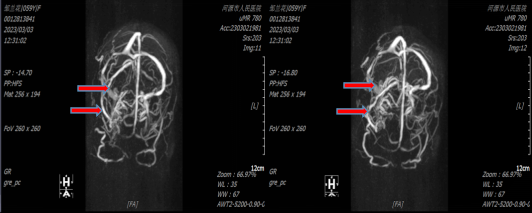

59岁的邹阿姨因2周前开始出现突发剧烈头痛到我院就诊,行核磁共振增强扫描检查提示桥小脑角区巨大肿物。

红色箭头为肿物,黄色箭头显示脑干受压变形,蓝色箭头显示有梗阻性脑积水

入院后进行头颅MRV检查(红色箭头提示右侧横窦受压缩小)可见肿瘤侵犯右侧横窦及乙状窦